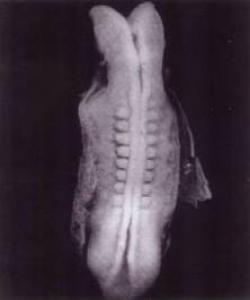

کرۆمۆسۆمهکان ئهو کۆده ههڵدهگرن که چالاکى خانه و دابهشبوونى ئاڕاستهدهکهن بهپێى ڕیزبوونى ترشه ئهمینیهکان، بهدرێژایى دوو شریتهکه له بۆشاییدا... (ئاشکرایه کۆرپهله یهکگرتنى خانهیهکى نێره((((((( سپێرم) و خانهیهکى مێیه هێلکۆکه)یه.

لێرهدا سیفهته بۆماوهییهکان به ههریهکه له کرۆمۆسۆمهکانى باوک و کرۆمۆسۆمهکانى دایک دیارى دهکرێن، ههریهکهیان بهڕێژهى (50%)، ئهوهش سهرهتا به نوتفهى یهکهم دهستپێدهکات، که سپێرم و هێلکۆکه کۆدهکاتهوه: ((نطفة أمشاج) نوتفهیهکى تێکهڵ.

(مشيج) واته دوو شتى تێکهڵکراو... کۆرپهلهى بهدیهێنراوى نوێ پێکدێت، وهک بهڵگهى ڕاستێتى ئایهته پیرۆزهکه: [